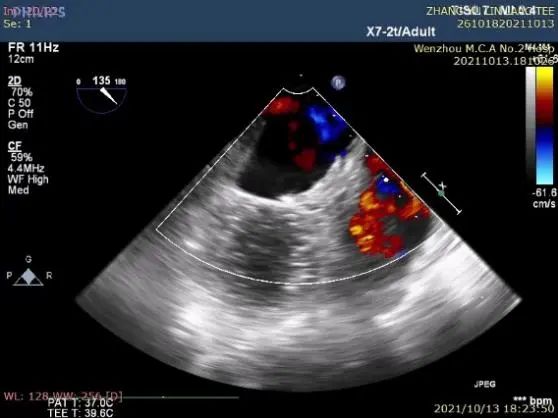

②左心耳封堵

行左心耳头位和足位造影,造影显示左心耳为菜花型。锚定区约为20mm,开口区约为24mm,依据选型原则,拟选LAmbre™2228封堵器或2430封堵器。

图1:RAO30° CRA20° 头位造影

图2:RAO30° CAU20° 足位造影